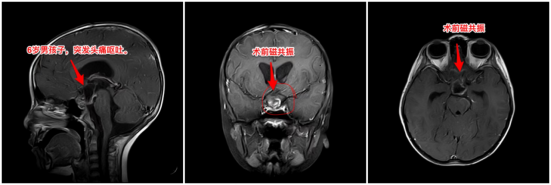

3月23日,周忠清主任接诊聪聪,查看相关影像资料,明确诊断为蛛网膜下腔出血,伴有颅咽管瘤、脑积水,肿瘤为囊性、有钙化。

周忠清主任表示,从影像资料上看,聪聪的颅咽管瘤属于造釉型颅咽管瘤,这种肿瘤本身不易出血,所以蛛网膜下腔出血一定另有原因,可能是脑子里隐藏着其它的“炸弹”。行核磁共振脑血管造影,未发现脑部明显出血诱因,于是决定先行脑室外引流术,降低颅压,情况稳定后行经额底纵裂入路切除颅咽管瘤,同时探查蛛网膜下腔出血的原因。